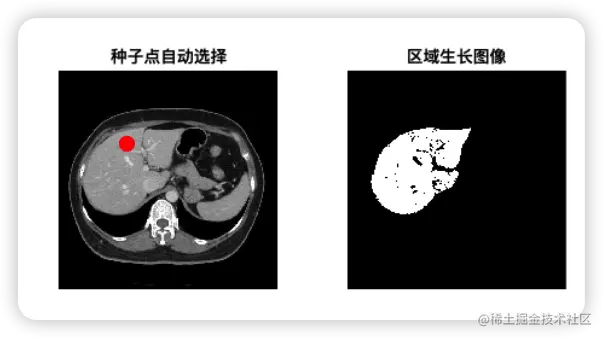

figure(1);

subplot(1, 2, 1); imshow(I, []);

hold on;

plot(seed_point(1), seed_point(2), 'ro', 'MarkerSize', 10, 'MarkerFaceColor', 'r');

title('种子点自动选择');

hold off;

subplot(1, 2, 2); imshow(J, []); title('区域生长图像');